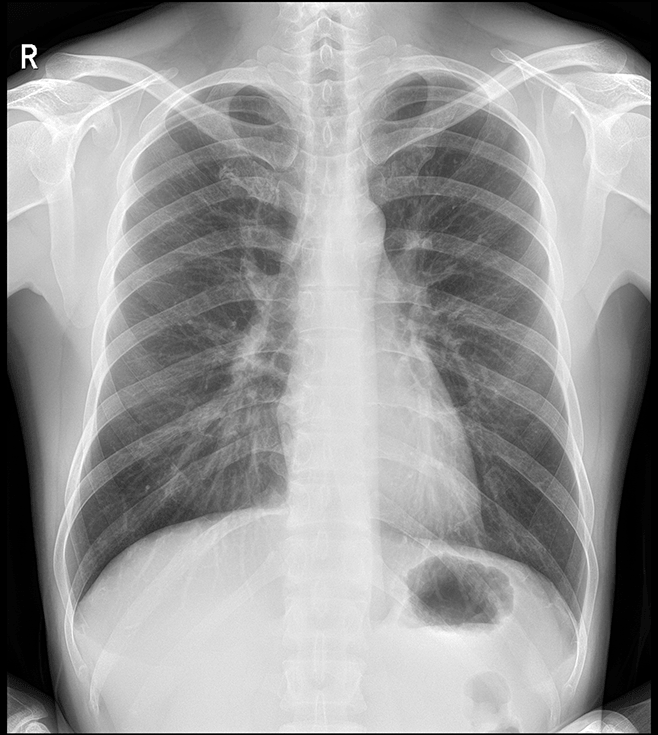

多功能诊断专用动态DR

太阳成集团tyc122cc入口科技全新设计的第四代床式动态DR,集拍片、透视、造影、全身拼接、尘肺体检于一体,一机多能,真正意义上实现全科室应用,提升医院实际效益。

高清动态平板探测器

搭载自主研发超清大视野动态平板探测器,600微米碘化铯大幅提升X线转化效率,独特的非晶硅阵列与高速读取集成电路紧密协作,轻松实现多帧率透视与高清点片。

专业的影像处理系统

“腾灵”系列搭载的IEAE影像处理系统,具备多项发明专利。本系统采用多频域图像处理技术,其6大核心处理模块使影像具有优秀的一致性、柔和性、空间层次感和纹理细腻度,为用户精准诊断病灶奠定了坚实的基础。